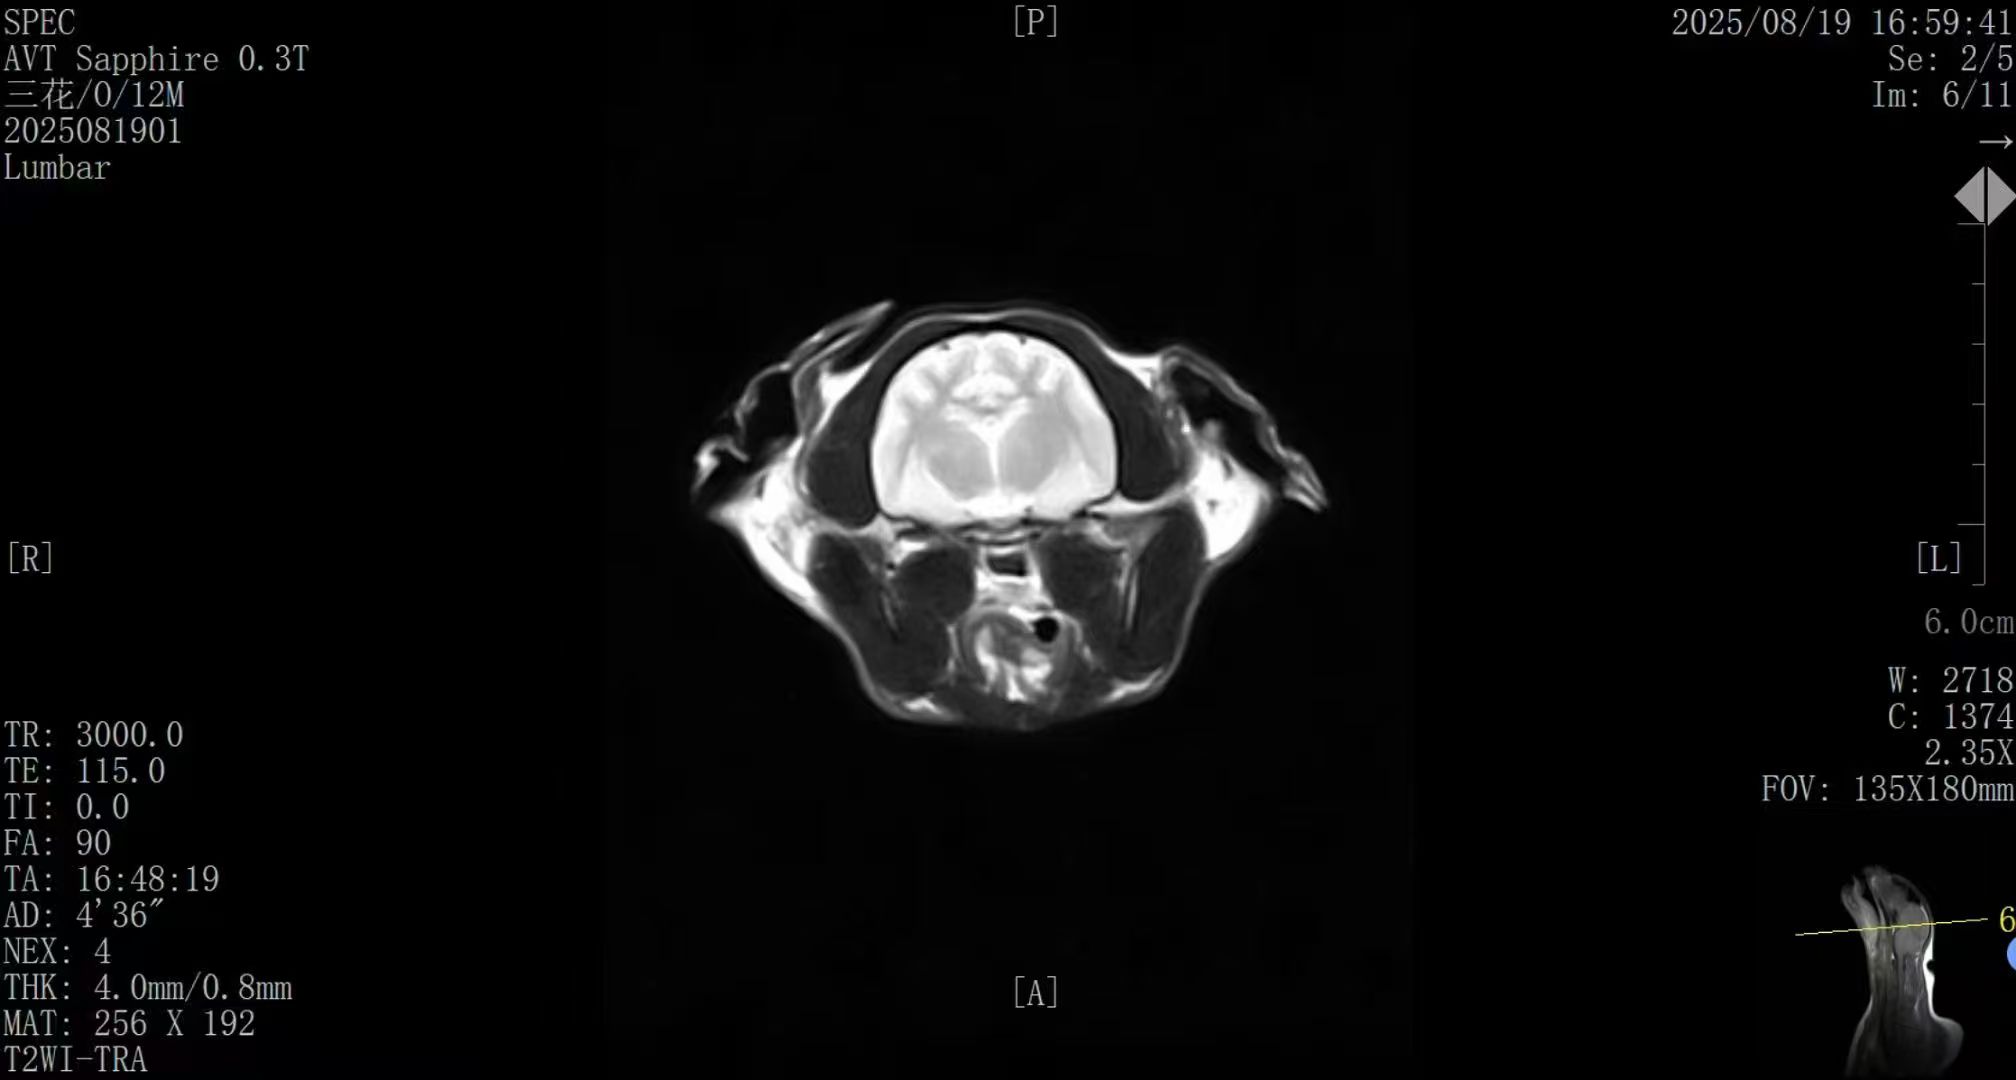

✅ AI智能成像 · 诊断更精准

搭载新一代AI影像优化系统,图像信噪比与组织对比度 整体提升约50%;

在神经、脊柱、关节及软组织等常见病例中表现优异,图像清晰、细节丰富,满足临床精准诊断需求。